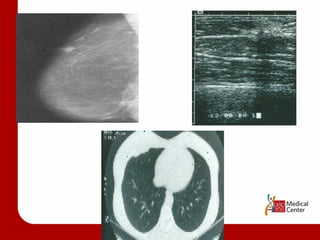

Imaging of Local Recurrence Mammography visualized:  3/5 Ultrasound visualized:  11/12 CT scan imaged:  3/3 MRI imaged:  1/1

Imaging of LocalRecurrence Mammography visualized: 3/5 Ultrasound visualized: 11/12 CT scan imaged: 3/3 MRI imaged: 1/1